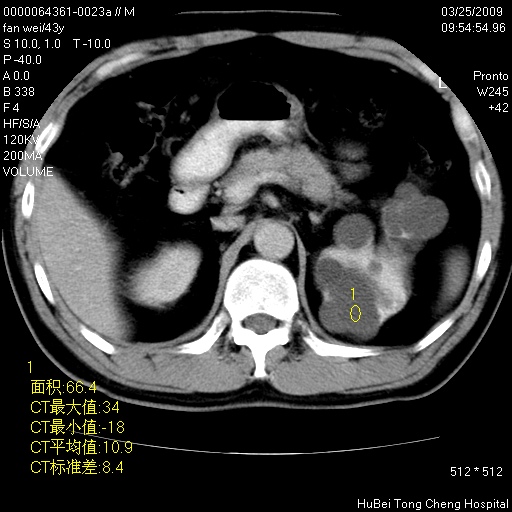

双肾ct轴位平扫+增强扫描(层厚10mm,螺距1.0,重建间隔10mm),图像如下:

多囊肾的影像诊断标准:有阳性家族史,年龄<30岁,单侧或双侧肾脏有两个肾囊肿;30~59岁,两侧肾脏各有两个肾囊肿;60岁以上,每侧肾脏有4个囊肿。敏感性和特异性达86%和80%。

此病例影像诊断符合,要结合家族史,腰痛、血尿、尿路感染史,有无高血压等综合判断,如无相应的临床症状,本身病变也无意义了(个人观点)

囊肿数得清,肾功能正常,考虑多发肾囊肿.另外,右肾后极突向肾周间隙的那个病灶是不是错构瘤,请楼主调窗看看.